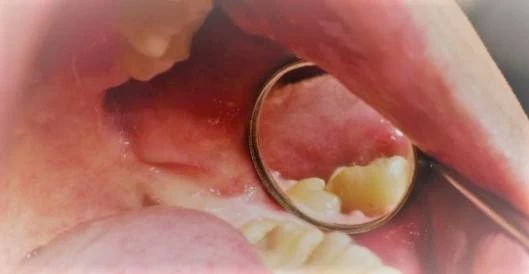

Poniżej przedstawiamy zabieg usunięcia zatrzymanego zęba mądrości wykonany przez specjalistę chirurgii stomatologicznej - dr Tomasza Kozioła, który polegał na znieczuleniu miejscowym, odsłonięciu zęba, zniesieniu blaszek kostnych z okolicy zęba, odcięciu korony i jej usunięciu, rozdzieleniu korzeni i ich usunięciu oraz zszyciu rany.